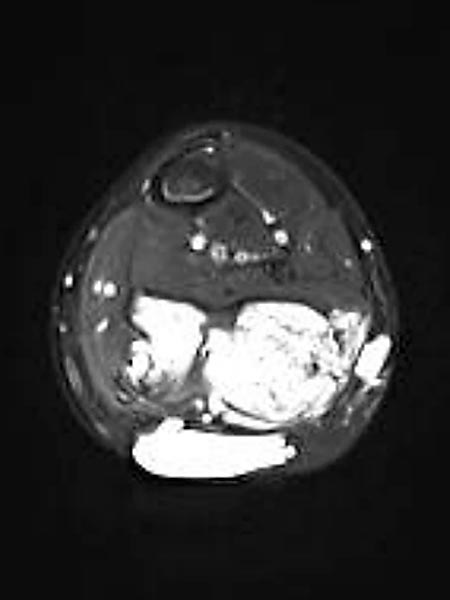

The second calf muscle (soleus muscle) is not affected in transverse, T2-weighted, fat-suppressed MRI. It must take over the power postoperatively. In addition, epifascial lymphatic malformation components are found.